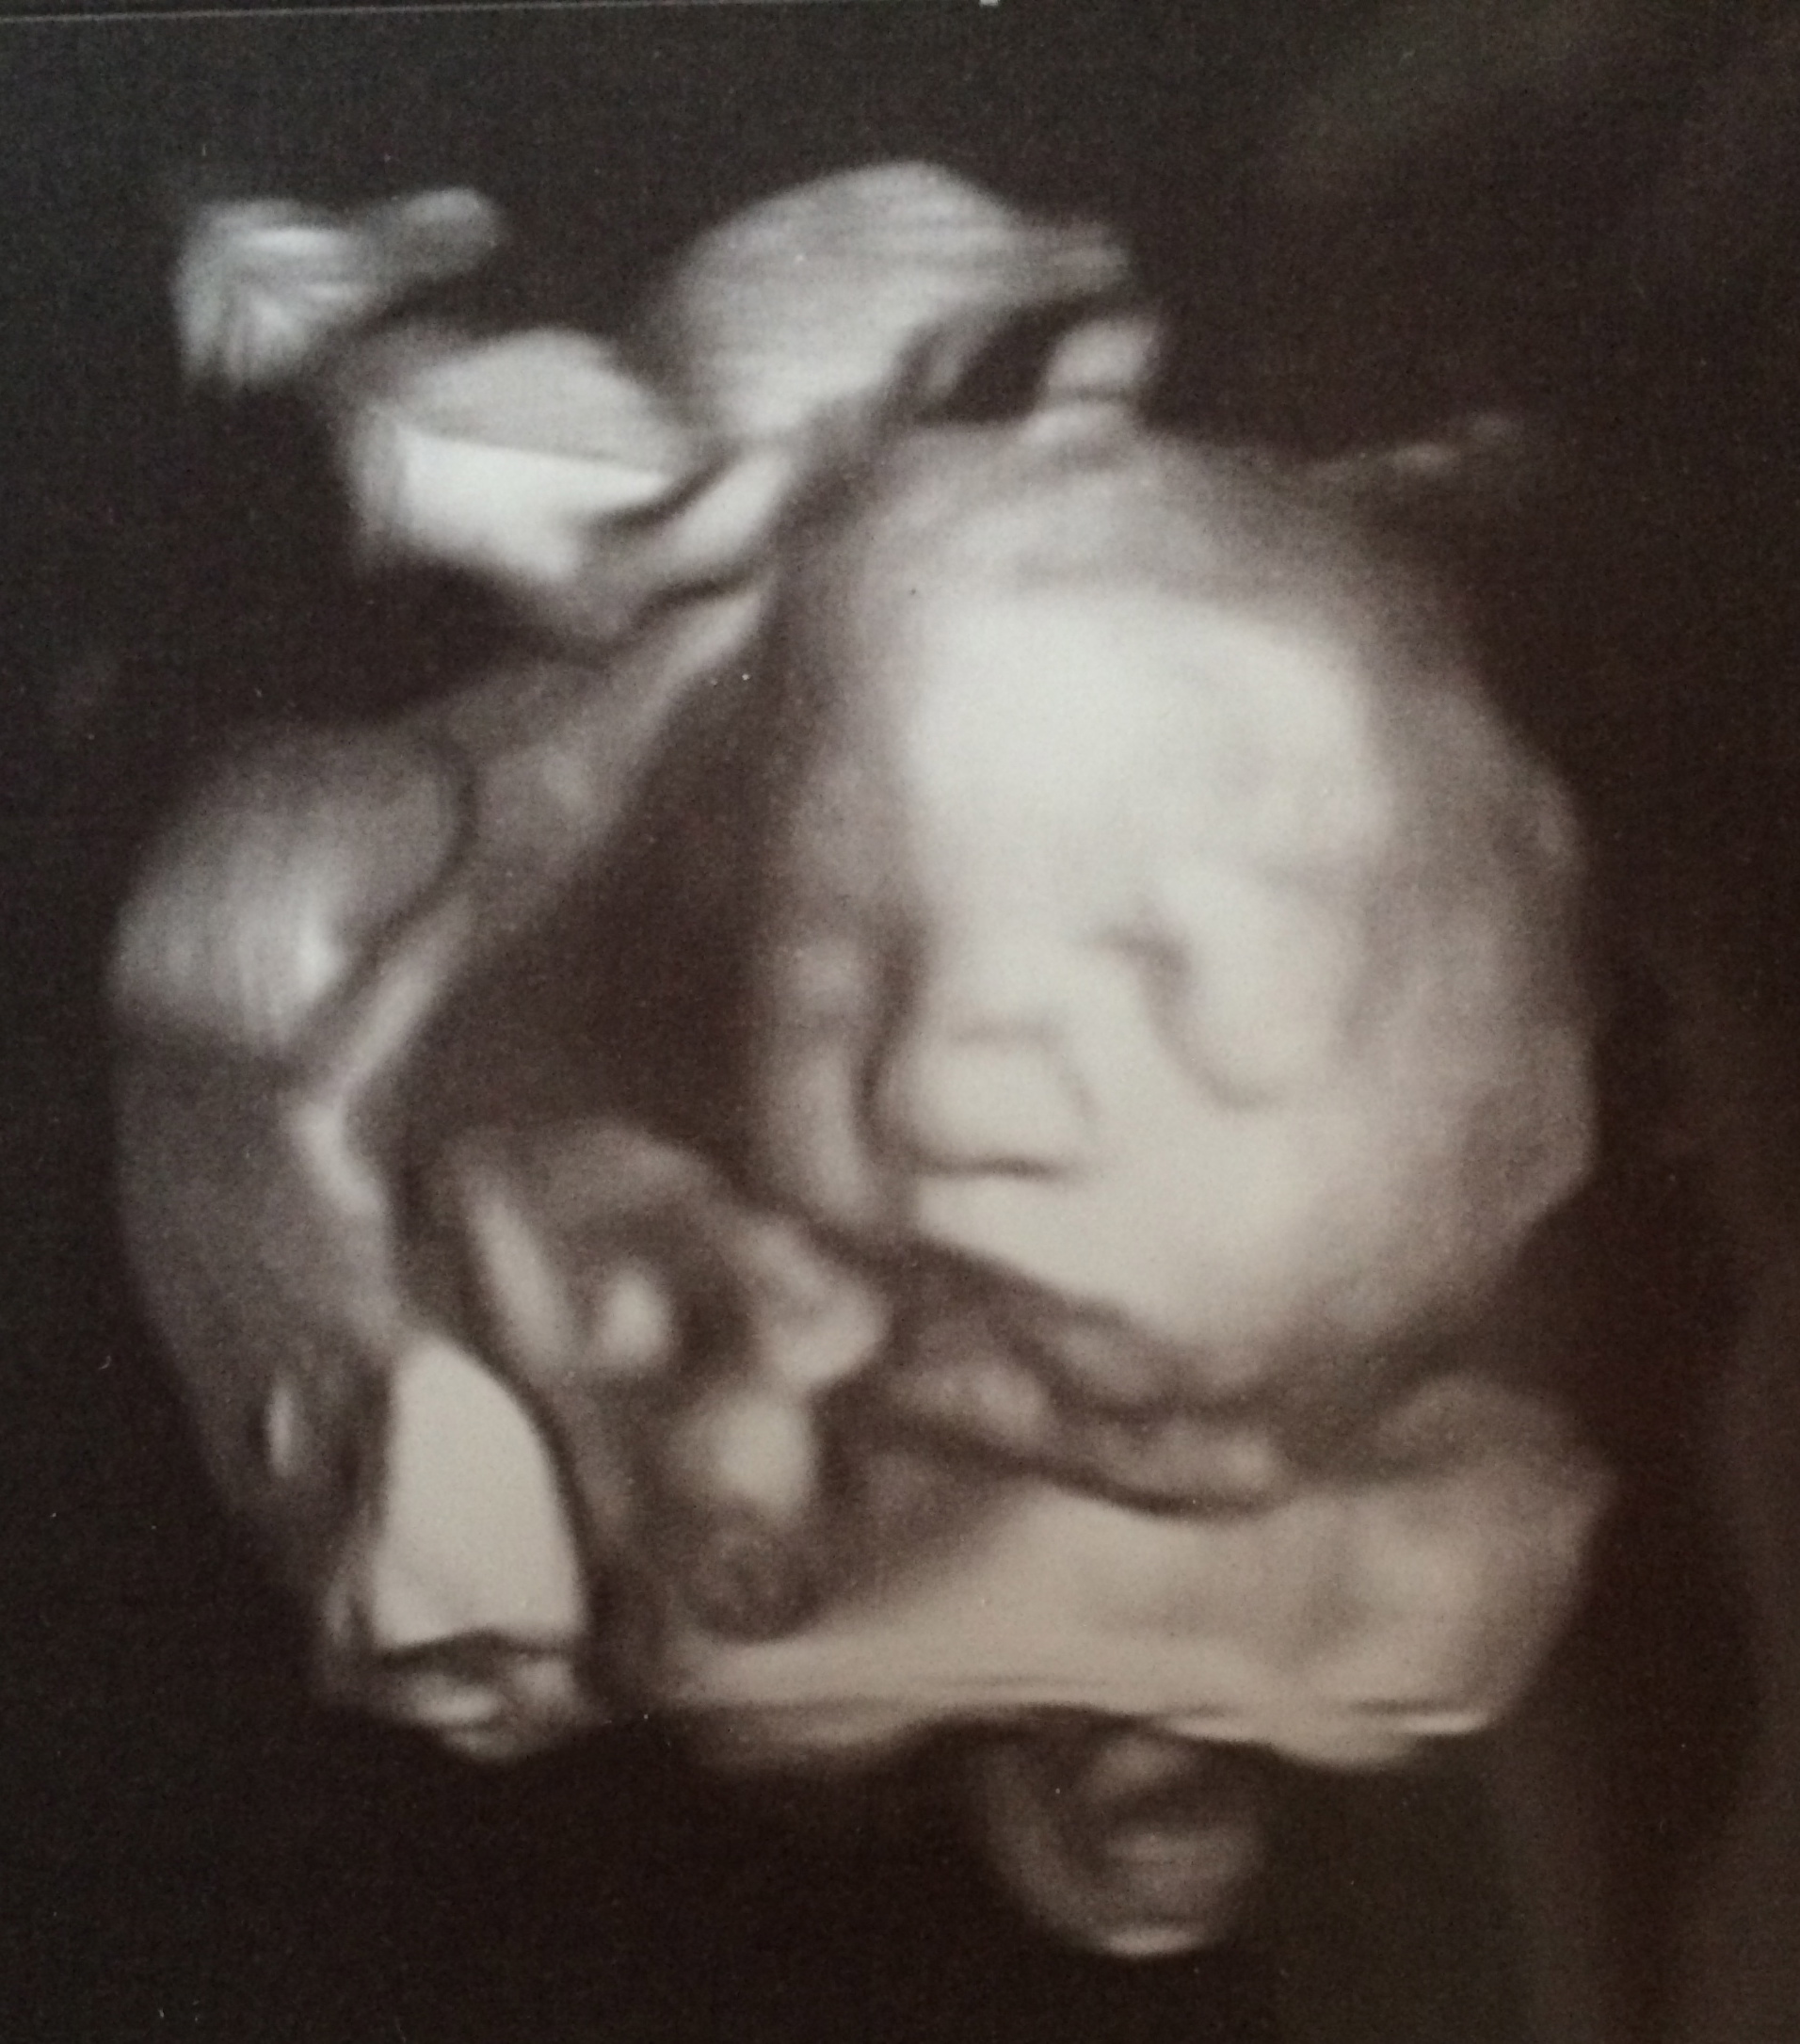

Any updates or appointments coming up you'd like to share? I just had an elective at a local college for the students final exams. We got some good 3Ds and she looks alot like her sister.

Any updates or appointments coming up you'd like to share? Just had my 27 week US last Thurs. Placenta moved!!! Super excited. Little one is still breech but not worrying. Got to see her in 3D which was so cool!!!

I had to share my 3D US. Some of you might have seen it on another post but, just super excited.

dragonfly711: I'm glad to hear your placenta moved!! And that is an amazing 3d picture, so cute.